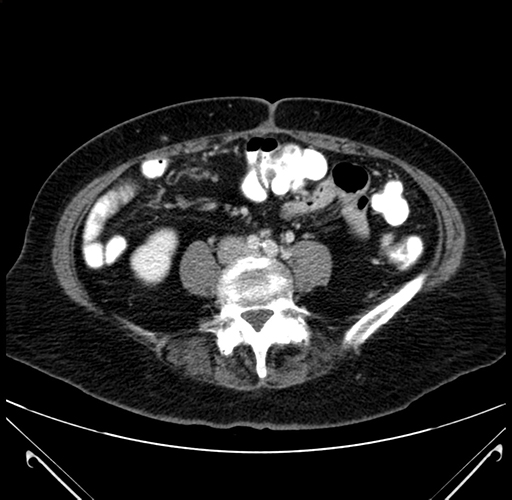

Pre-Chemo: Axial Venous

Axial Venous